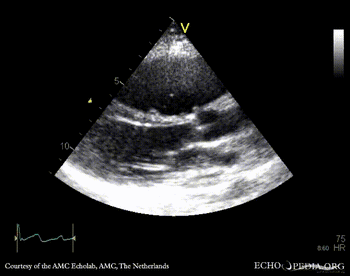

PLAX: enlarged right ventricle in patient with Ebstein anomaly A4CH: high insertion of tricuspid valve, enlarged right atrium and right ventricle